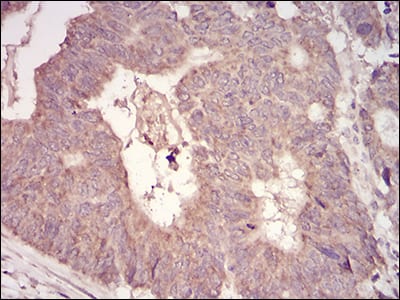

分类: 科研抗体货号: 30727别名: MCH3; CMH-1; LICE2; CASP7; ICE-LAP3;caspase 7;caspase7应用: WB,IHC,FCM反应种属: Human